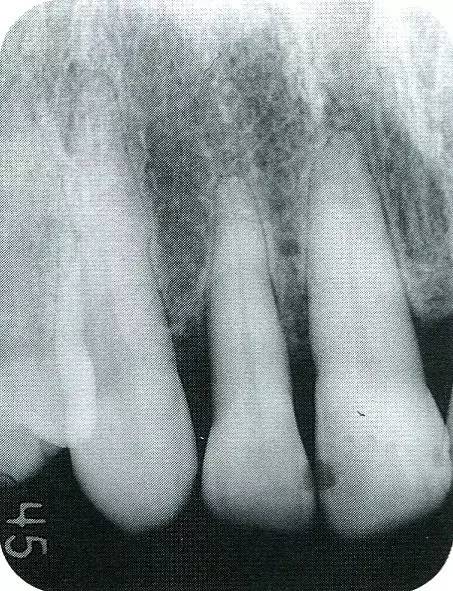

▲圖7-2  術(shù)前x片。確認存在垂直性深骨缺損。